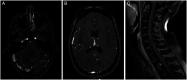

Figure 1.

Post-gadolinium MRI of the brain and spine. A, Axial preoperative post-gadolinium T1 weighted brain MRI demonstrated widespread leptomeningeal enhancement along the cerebellum and right temporal cortex (B) with extension throughout the CNS involving the surface of the spinal cord and associated diffuse osseus metastatic disease (C).